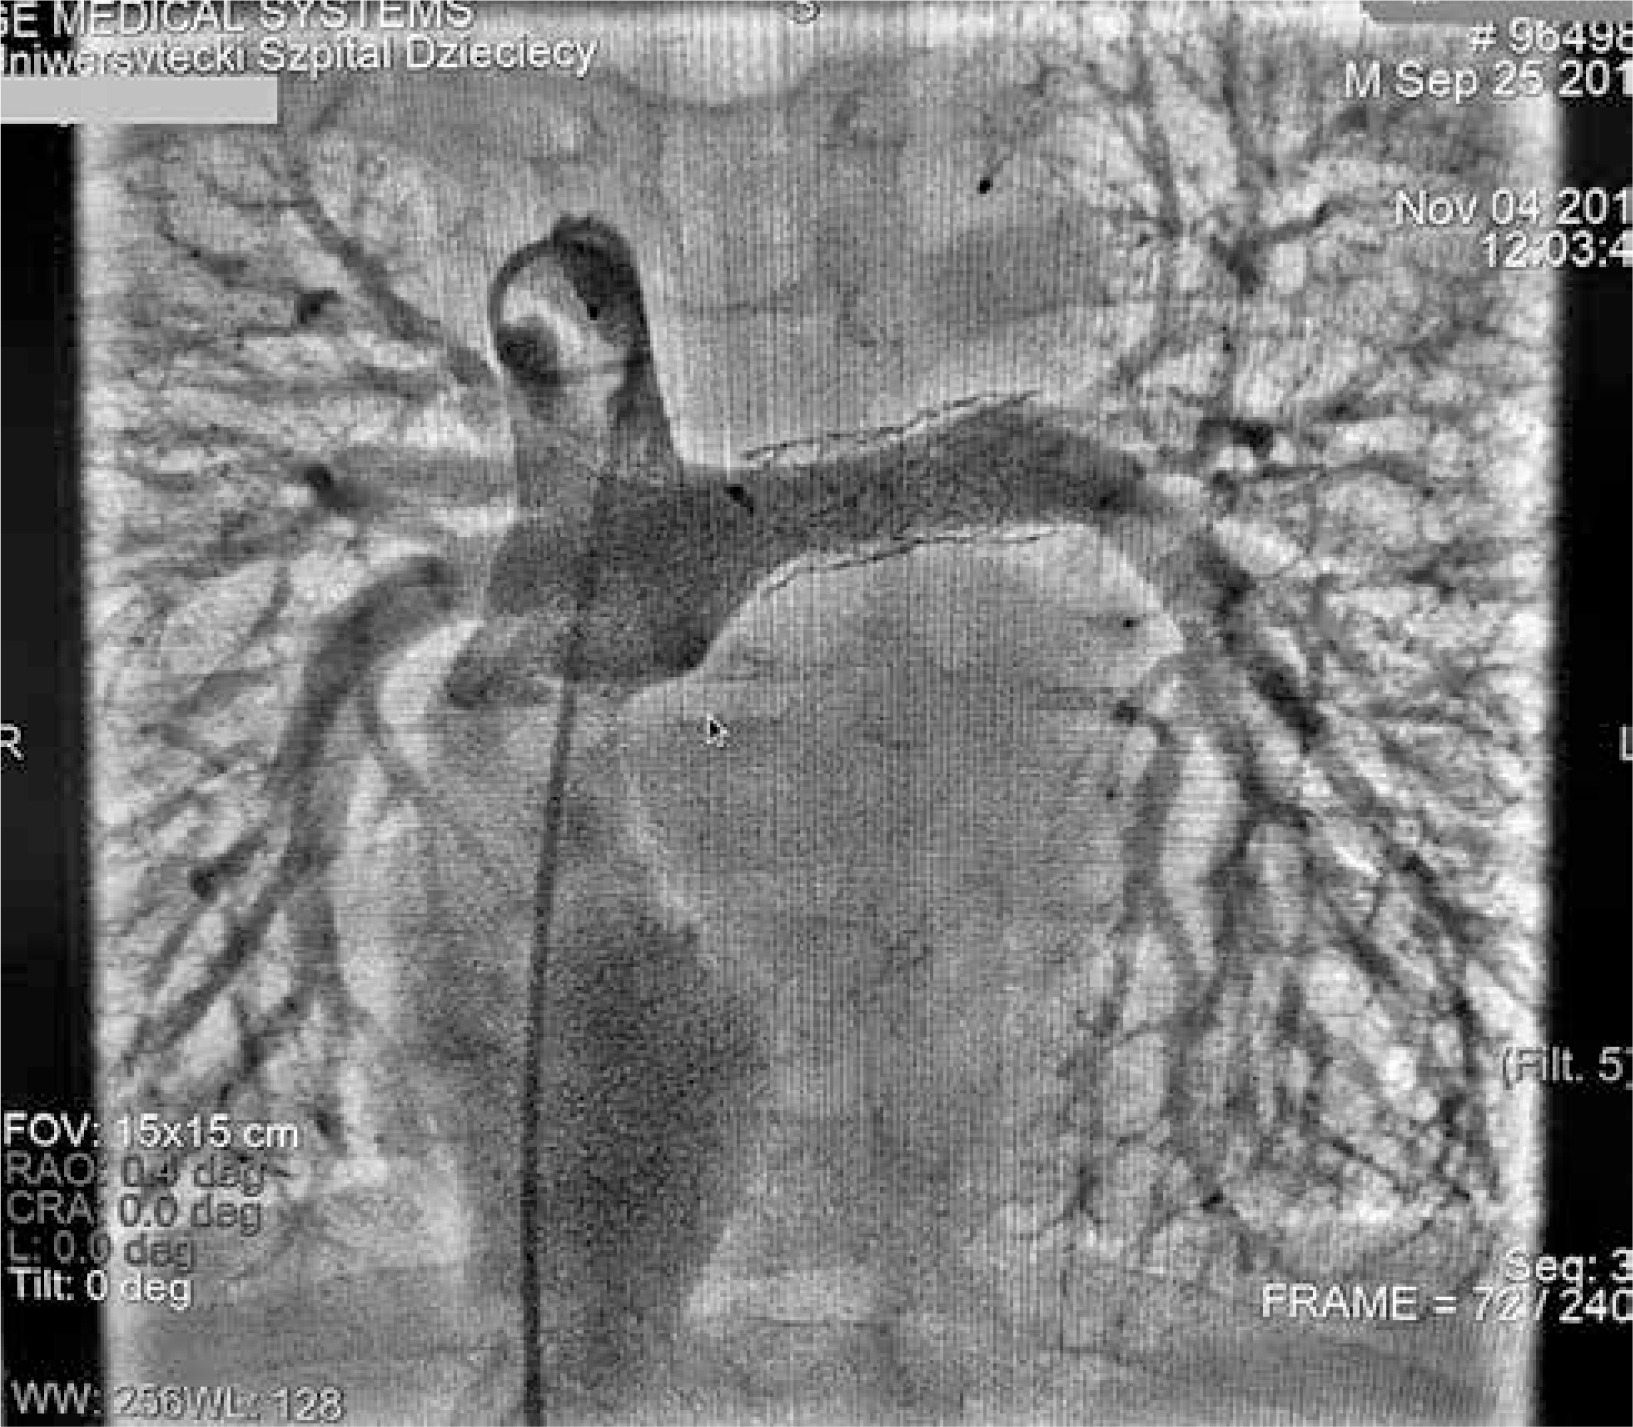

Figure 2

Angiography of the pulmonary arteries and Fontan tunnel. The tunnel measured 14.1 mm at its junction with the inferior cava vein, widened centrally to 26 mm and tapered to 10.9 mm at the junction with the pulmonary arteries. No fenestration was identified. The stent in the left pulmonary artery measured 9.8 mm proximally, increasing to 11.2 mm distally

Figure 4

Angiography of the pulmonary arteries and Fontan tunnel. The right pulmonary artery measured 8.1 mm and was dilated with the 12 mm balloon, and the left pulmonary artery had undergone stent re-dilatation to 10 mm. The Fontan tunnel was dilated to 3 cm in the central portion, and the fenestration with a stent showed right-to-left shunting. The hepatic veins and inferior vena cava were also significantly widened